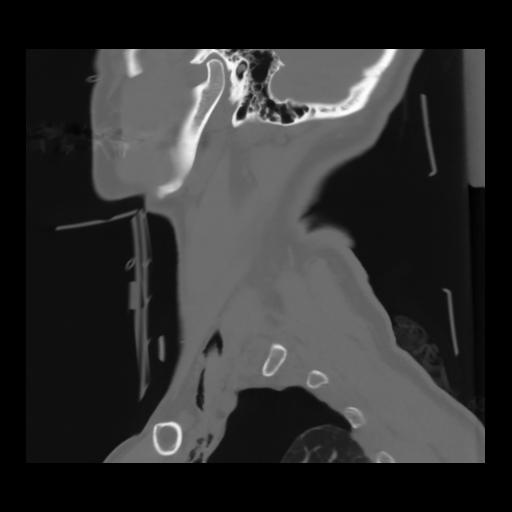

14 P.BLANDAS,,Sagittal,2.000,P.BLANDAS,Sagittal,